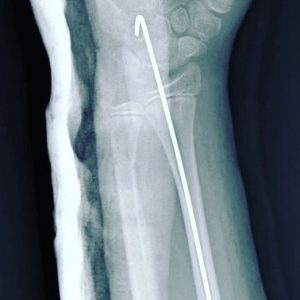

- Fracturas de codo

- Fracturas de antebrazo

- Fractura de radio y cubito

Fractura distal de radio

Fractura radiocubital

Fractura de radio distal